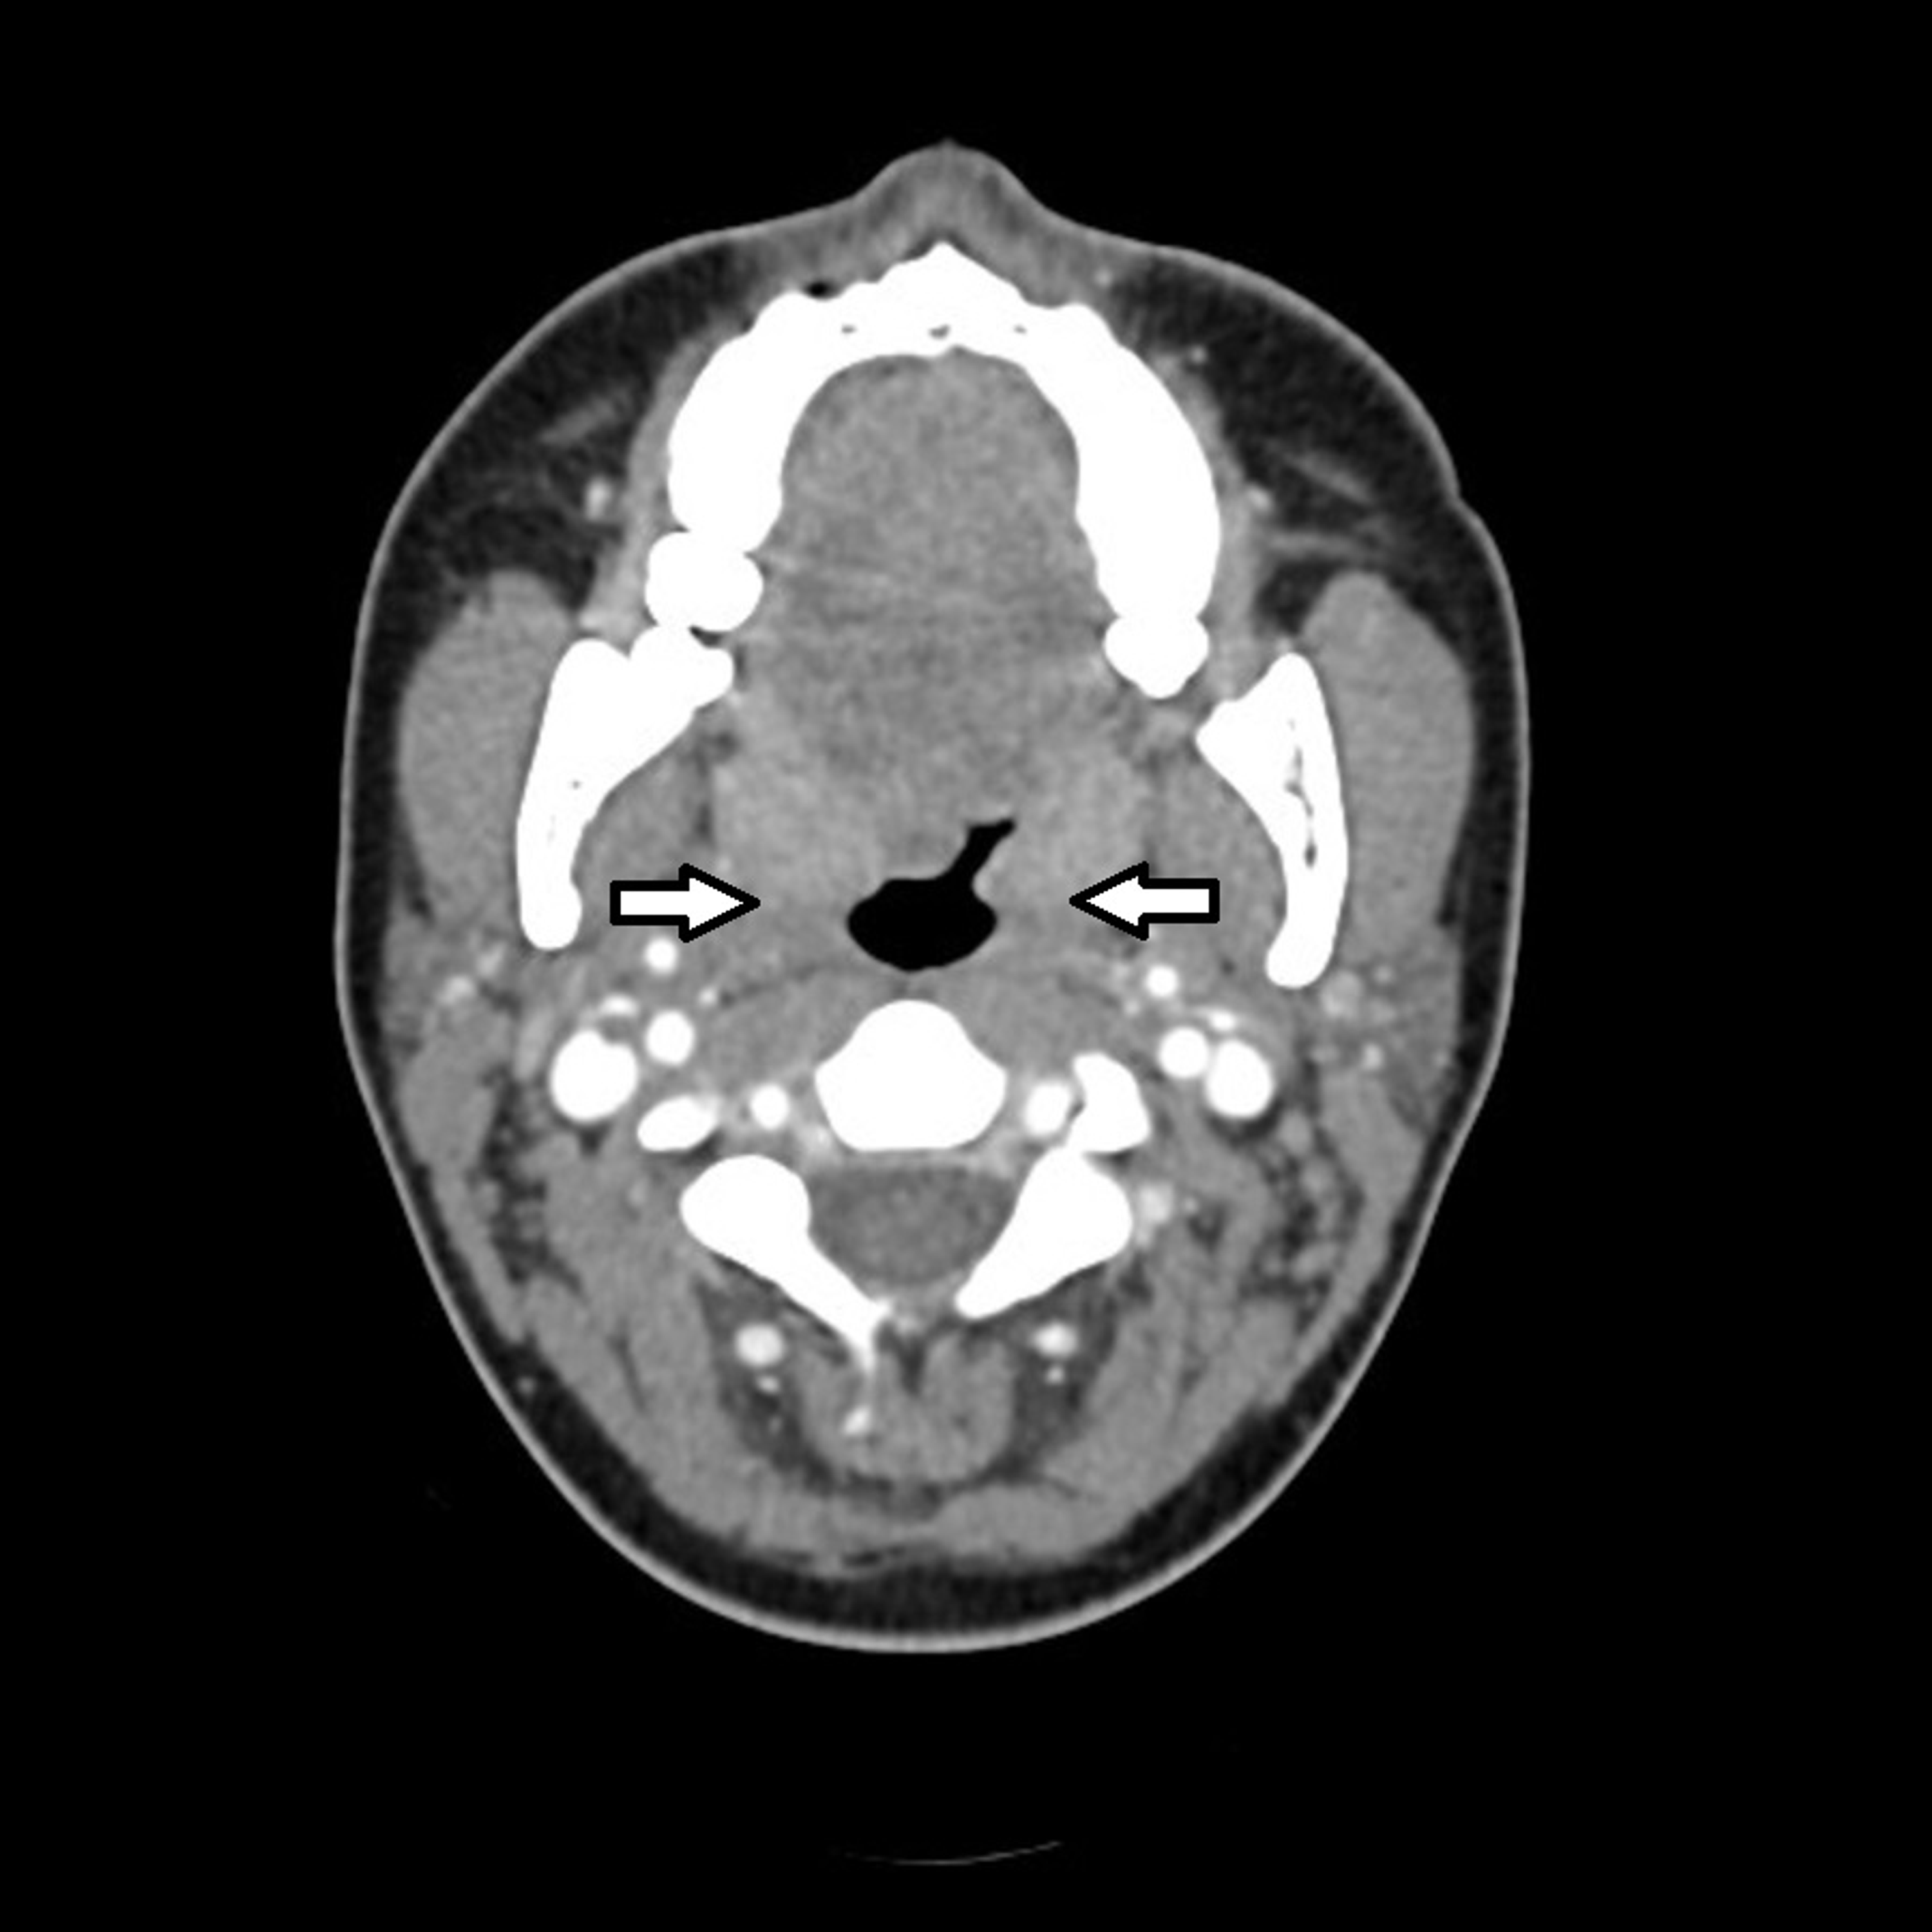

From www.researchgate.net

CT scan of the neck arrows ( ↑ ) show enlarged palatine tonsils Tonsils Labeled Ct The tonsils are collections of lymphatic tissue located within the pharynx. • the main imaging tools of the oropharyngeal region are computed tomography (ct) and magnetic resonance imaging (mri). Learn about its anatomy, function, pathology and radiological features on radiopaedia.org. They collectively form a ringed arrangement, known as waldeyer’s ring: Tonsils are lymphoid tissue aggregates situated near the entrance of.. Tonsils Labeled Ct.